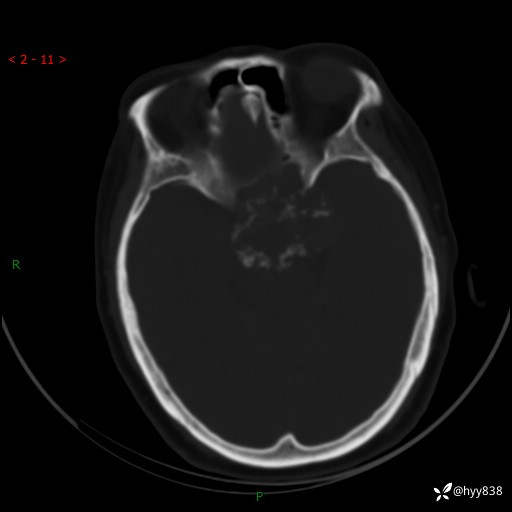

老年女性,视力下降3年。鞍区钙化性肿块,鉴别诊断有哪些---(有结果)

简要病史:患者3年前无明显诱因左眼出现视力下降,出现视物模糊,无头痛,无头晕,无恶心、呕吐,无意识障碍,无肢体麻木及抽搐,无心慌、胸闷,无腹痛、腹胀等不适,无旋地转感。个月前右眼视力下降,患者视物模糊逐渐下降,自诉看东西有雾感。在当地医院眼科就诊,症状无好转,行头部MR提示:鞍区肿物。现患者为求诊治来我科就诊,在当地市中医医院行头部CT:提示鞍区占位。患者现求进一步诊治来我院就诊,门诊以“鞍区肿物”收入我科。 患病以来,患者精神、饮食、睡眠尚欠佳,大小便如常,体力体重无明显变化。

临床诊断:鞍区肿物

颅脑CT平扫